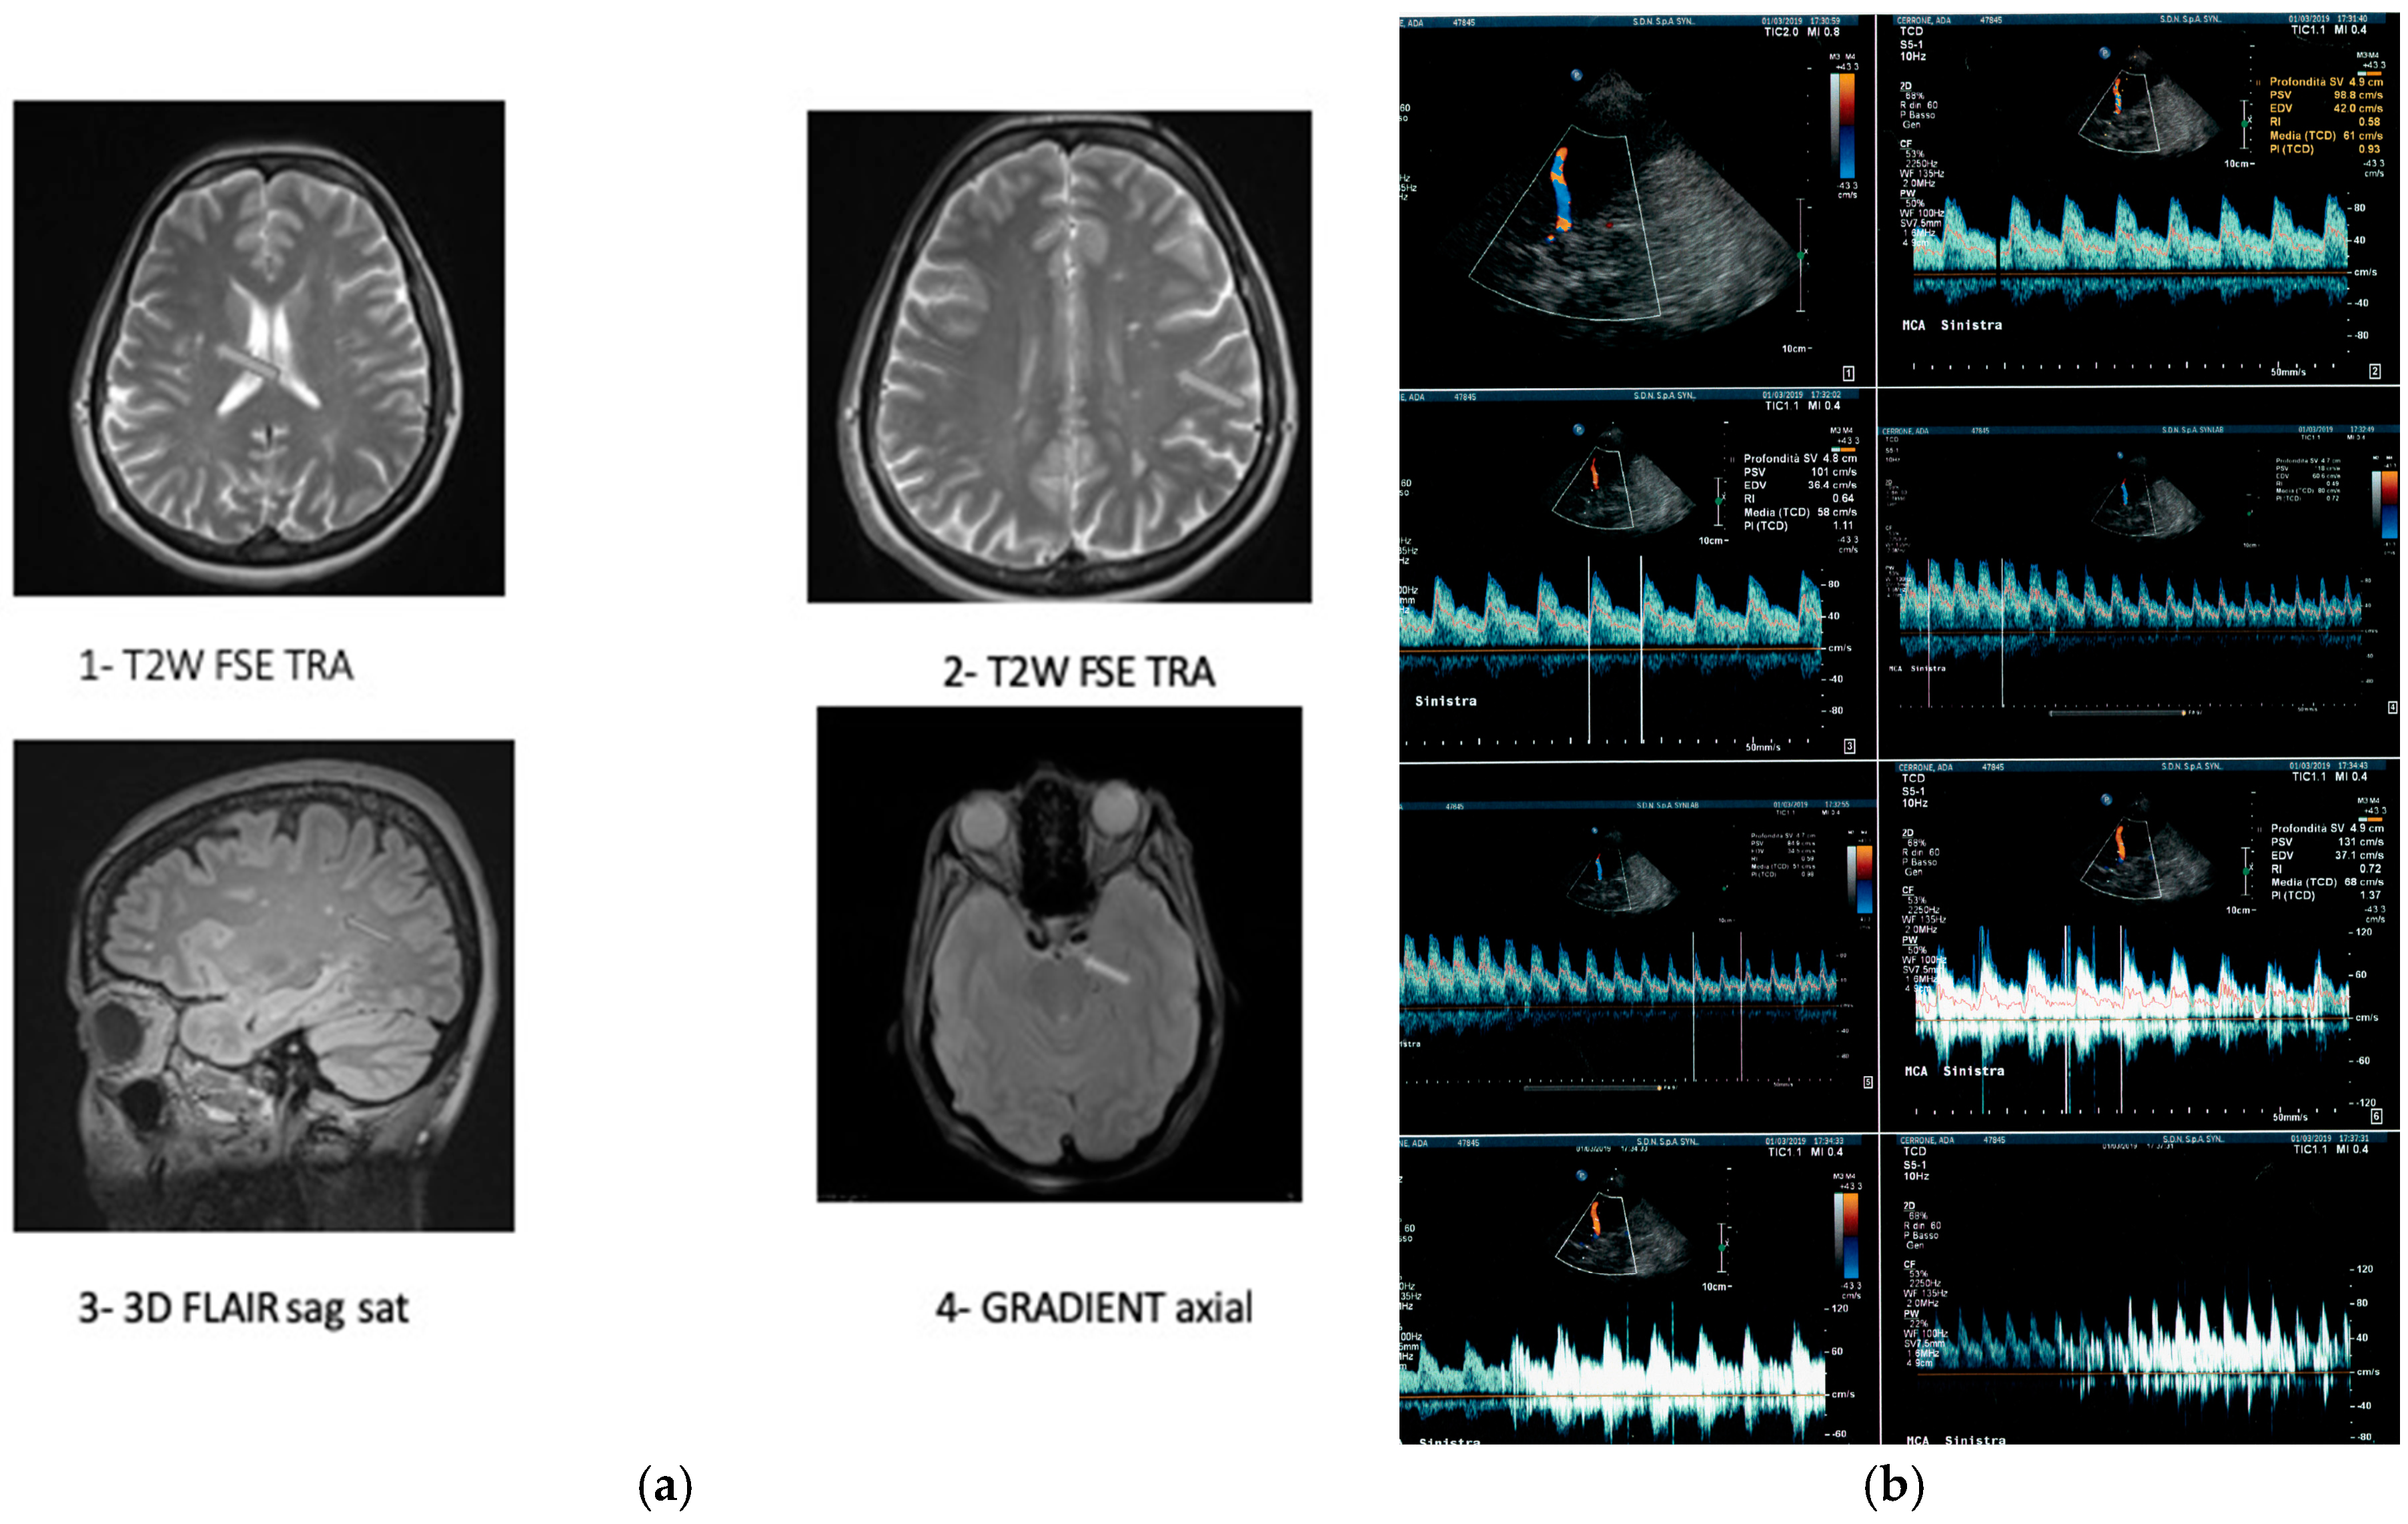

2. Presentation of the Case